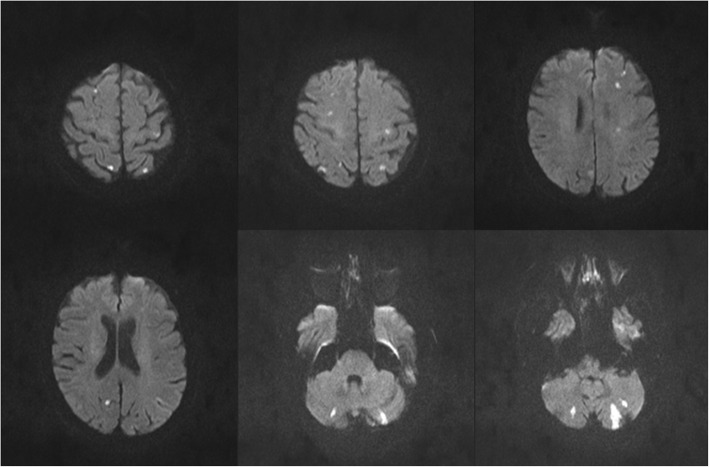

Brain magnetic resonance imaging (MRI) 2 days post stroke showed multiple small ischemic lesions bilaterally in the cerebellum as well as in subcortical and cortical areas of the cerebral hemispheres, affecting the supplying territory of arteries in the anterior and posterior circulation on both sides (Fig. 1). With regard to the cardioembolic pattern of the infarct lesions (Fig. 1) and - until this point - missing cardiac source of emboli, a bubble test by transcranial color-coded duplex sonography (TCCD) was performed, which couldn’t determine a right-to-left cardiac shunt.

Fig. 1.

Axial DWI-MRI displaying hyperintense signals in both hemispheres in the cerebral cortex, subcortex and in the cerebellum